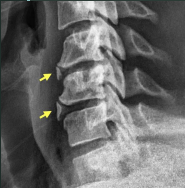

AP Open Mouth: Eval Criteria

Entire odontoid process, atlantoaxial joint, and lateral masses of C1 demoed

Upper incisors and base of skull are superimposed

Atlantoaxial joint is symmetrical

AP Open Mouth: Is this Image Good?

No.

Base of skull superimposed over dens and lateral masses

Atlantoaxial joint is not clearly demoed

Extensive extension of skull

Reposition by slight flexion of the neck or angle the CR slightly caudal

Front incisors are superimposed over C1-C2

Atlantoaxial joint is not demoed

Excessive flexion of skull and neck

Reposition with slight extension of the neck or angle the CR slightly cephalic

How does rotation manifest on an AP Open Mouth odontoid?

Asymmetrical lateral masses and off-center alignment of spinous process of C2

To accomplish proper flexion or extension of the head and neck for an AP Open Mouth Odontoid, the ___ and ___ should be superimposed.

Upper incisors and base of skull

For AP Open Mouth Odontoid imaging, the base of the skull and/or the upper incisors will be projected about 1" for every ____ angulation.

5 degrees caudal